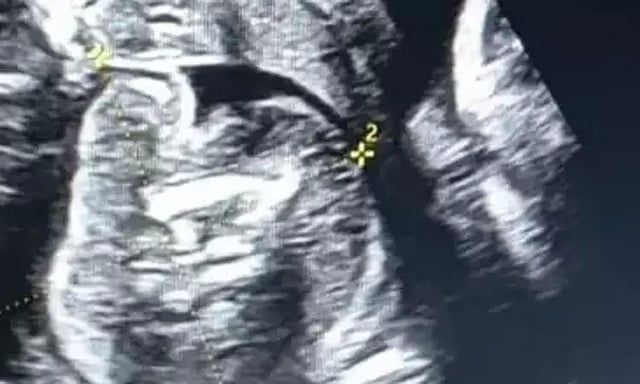

இந்த நிலையில் குழந்தையின் வயிறு சற்று பெரியதாக இருந்தது. இதையடுத்து அந்த குழந்தைக்கு மருத்துவ பரிசோதனை செய்யப்பட்டது. இதில் அந்த பச்சிளம் குழந்தையின் வயிற்றில் கரு வளர்வது கண்டறியப்பட்டது. இதையடுத்து டாக்டர்கள் அந்த குழந்தையின் வயிற்றை எம்.ஆர்.ஐ. ஸ்கேன் செய்தனர்.

இதுகுறித்து கிம்ஸ் ஆஸ்பத்திரி மருத்துவ அதிகாரி ஈஸ்வர் ஹசாபி கூறுகையில், பிறந்த குழந்தையின் வயிற்றில் கரு வளர்வது தெரியவந்துள்ளது. முதுகெலும்புடன் கூடிய கரு இருக்கிறது. தற்போது எம்.ஆர்.ஐ. ஸ்கேன் எடுத்துள்ளோம். அதன் அறிக்கை வந்ததும் அடுத்த கட்ட நடவடிக்கை குறித்து முடிவு செய்வோம். இது ஒரு அரிய நிகழ்வு என்றார்.